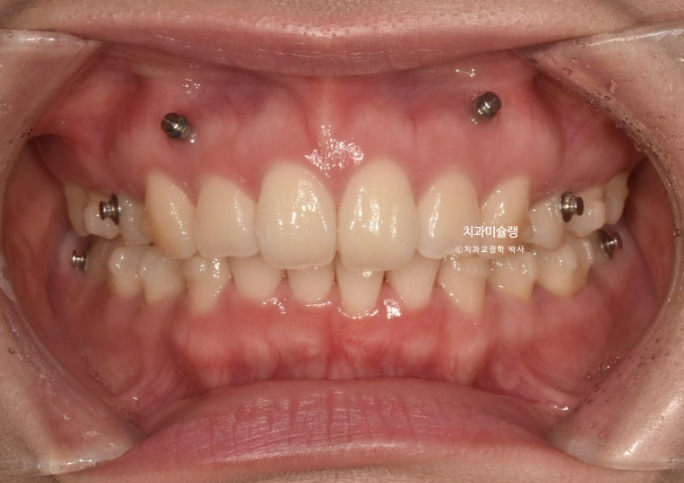

중심선은 정확히 맞아졌습니다.

발치공간도 거의 없어졌습니다.

그러나 발치한 부분에 치실이 헐겁게 들어갈 정도의 미세한 공간이 남아 3번째 재제작을 하기로 합니다.

25년 7월부터 26년 1월까지 15개 추가장치를 겨우겨우 모두 낀 후 치료를 마무리 했습니다.

26.01

총 치료기간은 3년 2개월, 재제작은 3회 했습니다.

어금니 교합은 뜨는 곳 없이 좋습니다.